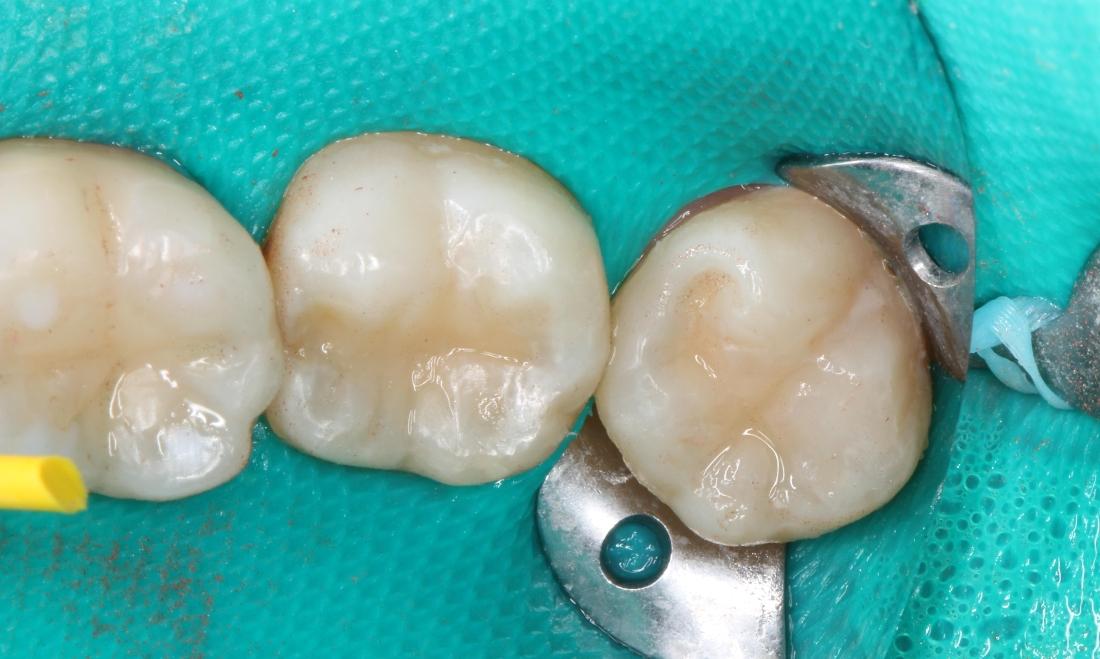

Our patient was having sensitivity on several teeth while eating and drinking sweet things. We found several large cavities in the pits and grooves of her molars. We used a green dental dam to isolate the teeth and prevent anything from contaminating the teeth. We then removed the cavities and rebuilt the teeth using white, tooth-colored composite filling material. We adjusted the bite after removing the dental dam and polished to make sure there were no rough areas. These fillings should last a long time with excellent home care and routine cleanings.